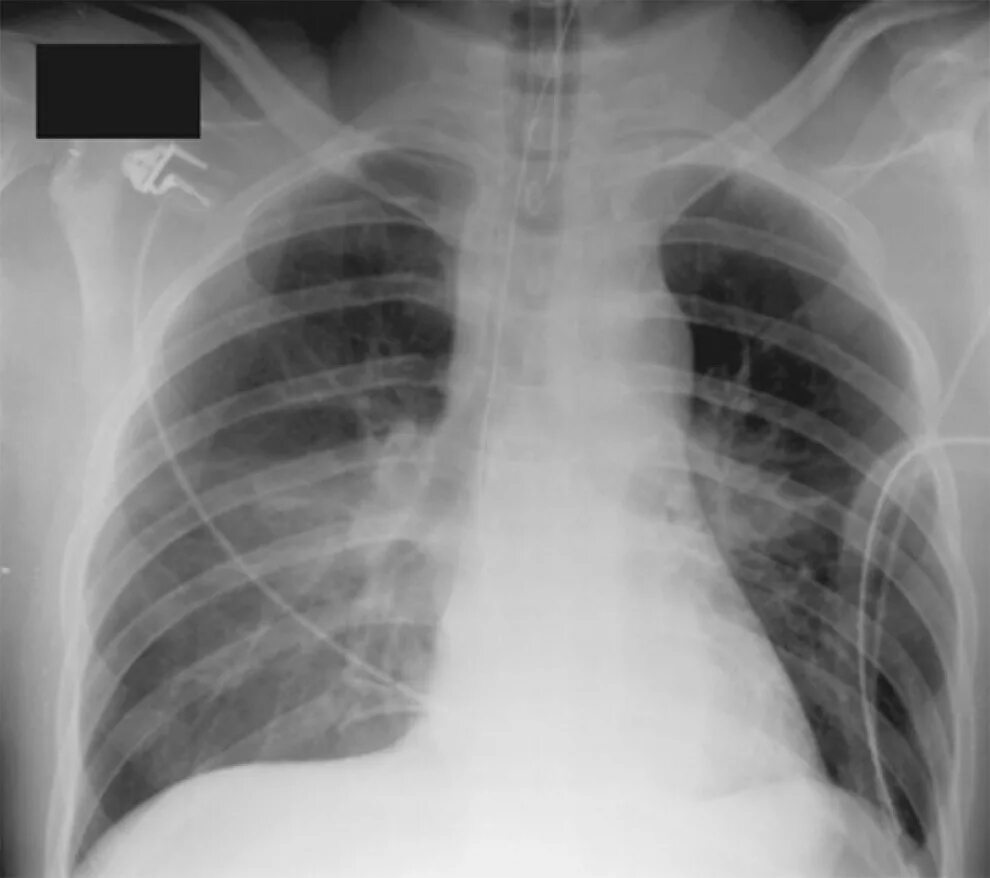

От чего бывает разрыв аорты